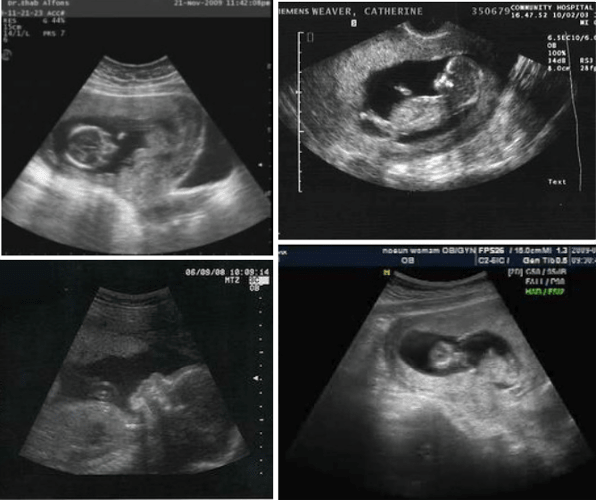

top showcases captivating images of ultrasound at 3 weeks pregnant pictures galleryz.online

ultrasound at 3 weeks pregnant pictures

Ultrasound images of embryo or fetal development at various stages of …